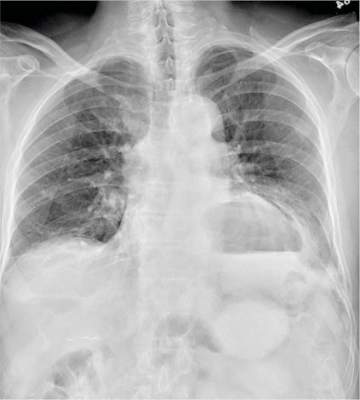

A 75-year-old man is brought to your emergency center following a fall from his attic. He slipped and fell approximately 10 feet, landing on his left side. He did not hit his head and denies any loss of consciousness. His primary complaint is left-side chest wall pain. Medical history is significant for hypertension, diabetes, reflux, and atrial fibrillation. On primary survey, you note an elderly male who is somewhat uncomfortable but in no obvious distress. His vital signs are stable; O2 saturation is 98% on room air. The patient exhibits moderate tenderness along the anterior lateral aspect of his chest, as well as mild generalized tenderness in his abdomen. Good inspiratory effort is limited secondary to his pain. While you enter orders into the computer, a portable chest radiograph is obtained. What is your impression?

The radiograph has several findings. First, there are multiple fractures along the left lateral ribs. Second, there is a small left apical pneumothorax. Most significant, though, is an elevated left hemidiaphragm. There appears to be stomach or possibly bowel protruding into it.

Although a large hiatal hernia could yield similar findings, in the setting of trauma, one must be concerned about a traumatic diaphragmatic hernia. Subsequent CT of the chest, abdomen, and pelvis confirmed a defect within the diaphragm, with a significant portion of the stomach herniating into the left chest.